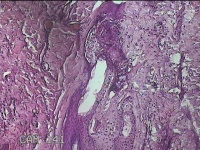

左侧会阴部皮下结节

性别

女

年龄

45岁

临床诊断

皮下结节

一般病史

发现左侧会阴部皮下结节2年余,伴近日局部隐痛不适。

标本名称

大体所见

灰白暗红色结节0.8x0.7x0.3cm一个,表面糜烂。

图1